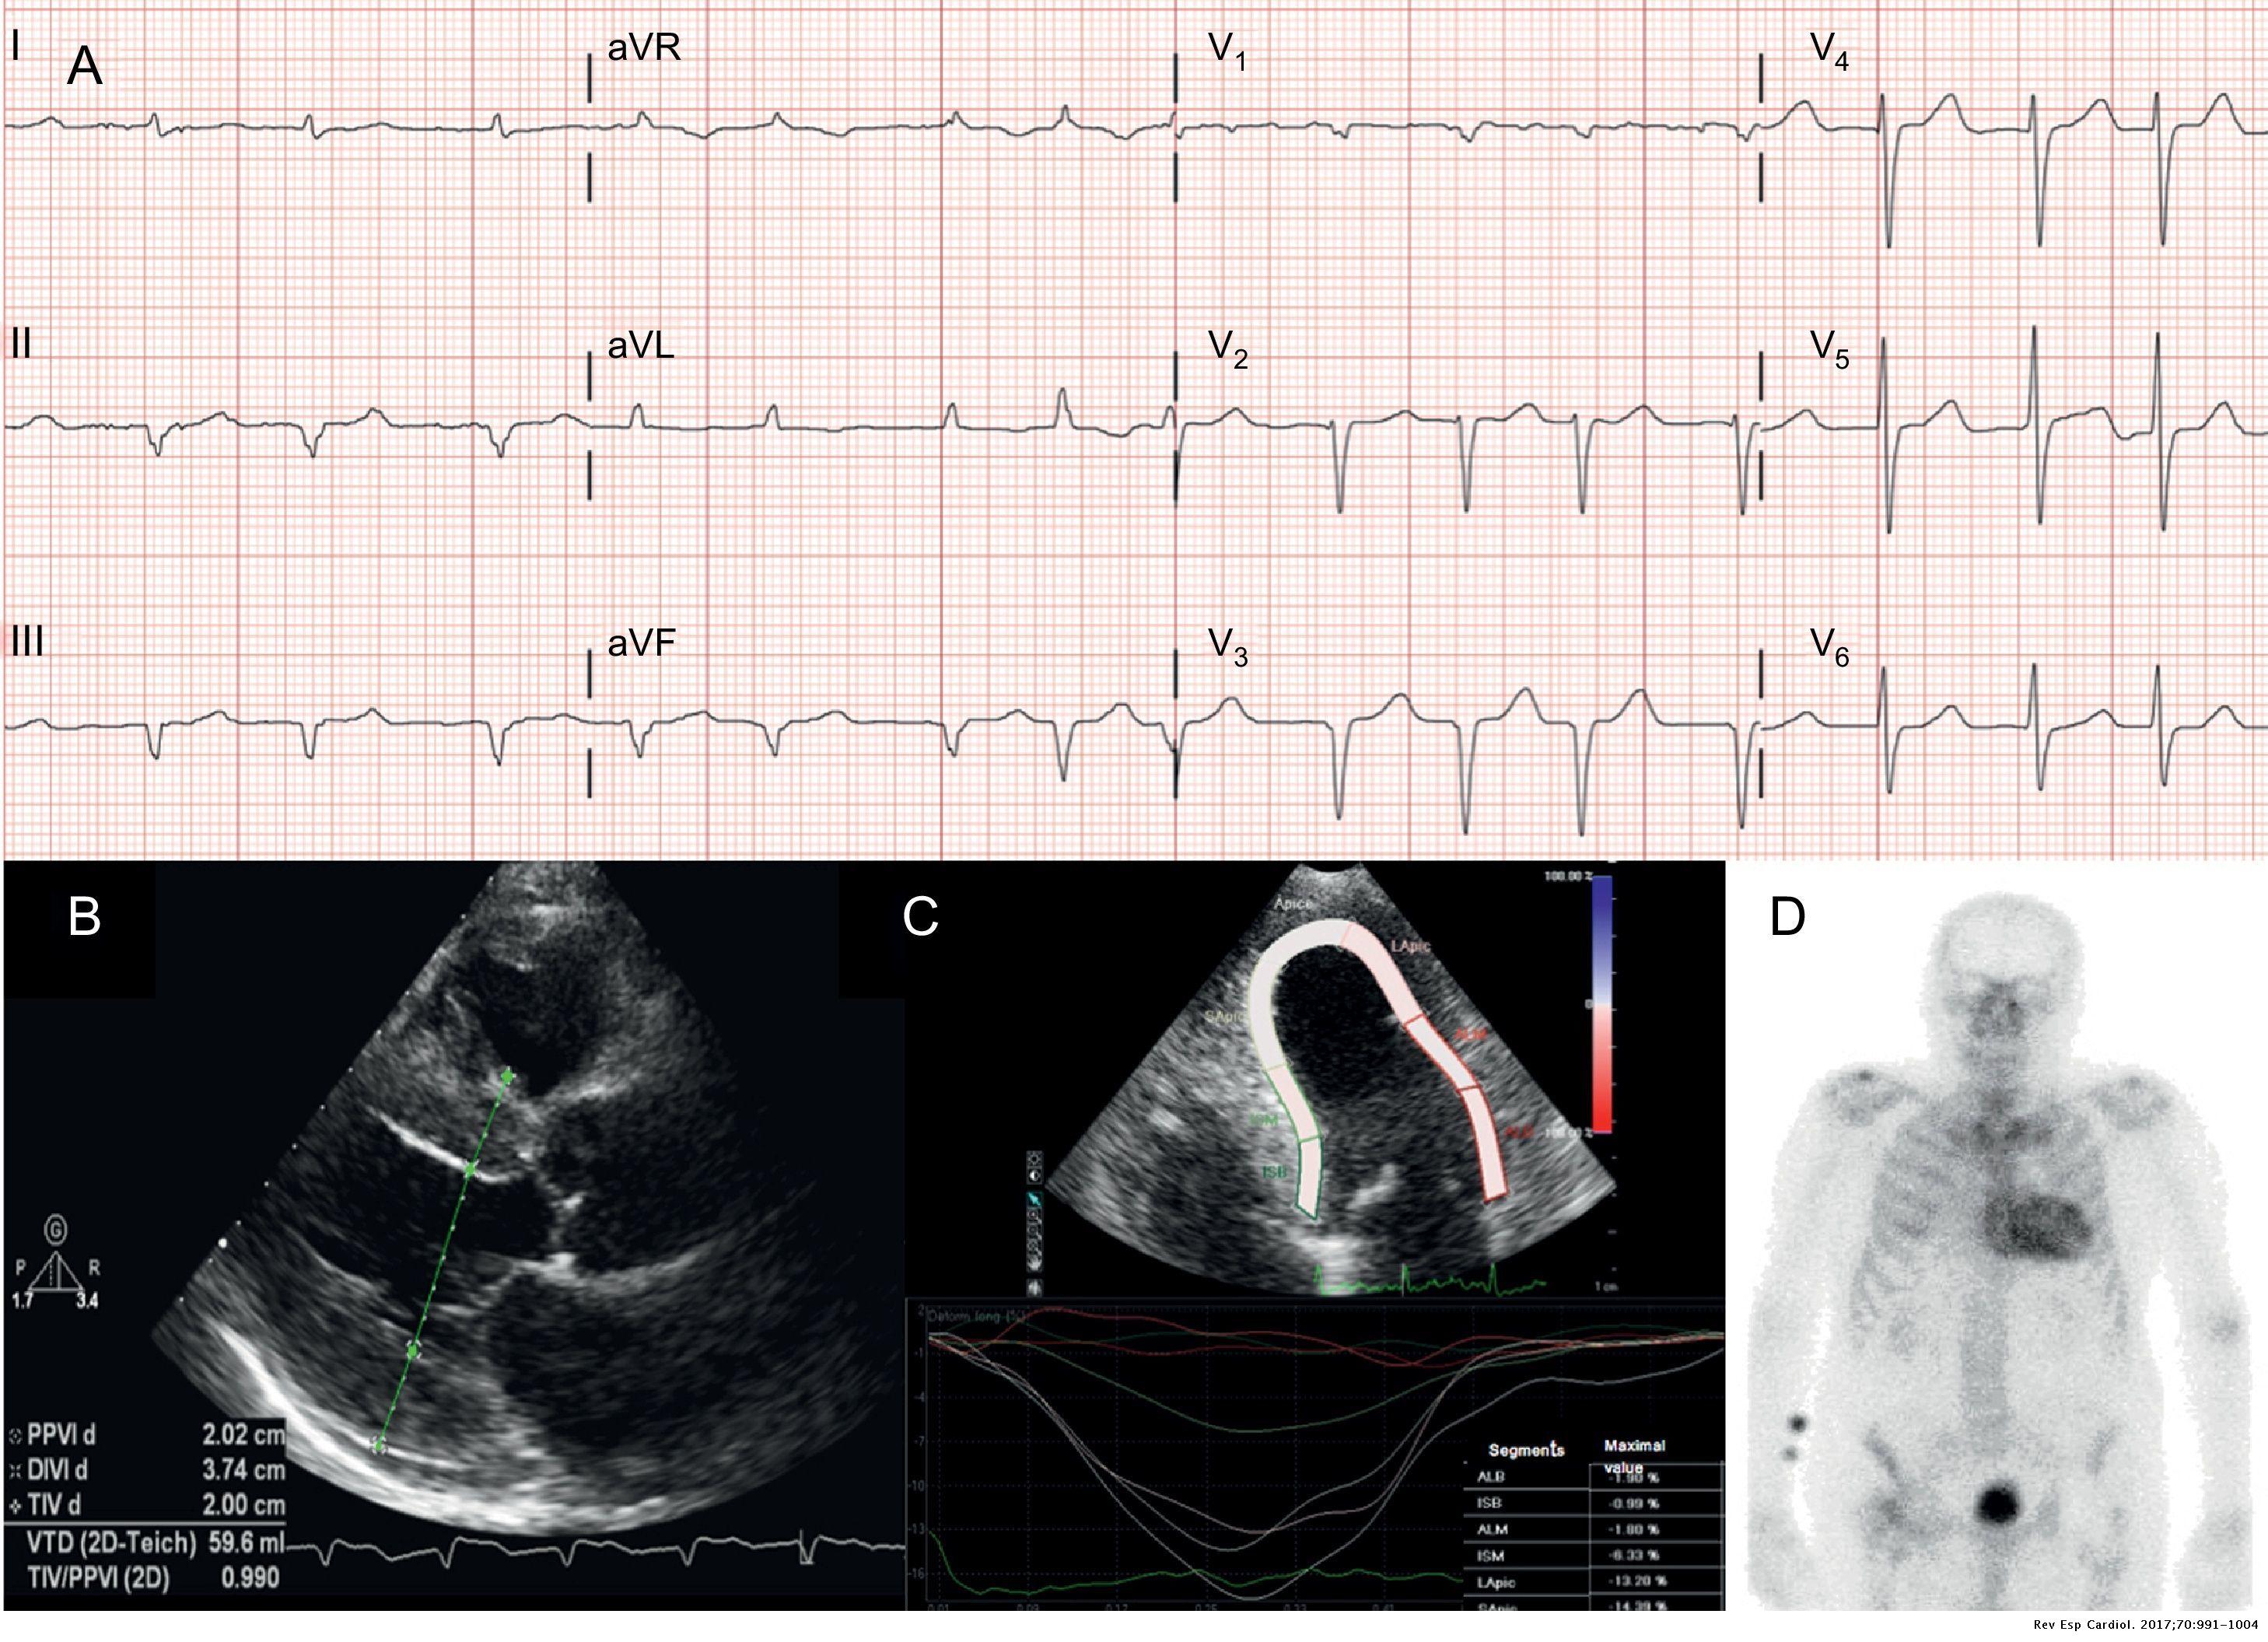

Amiloidosis cardíaca a través de la imagen multimodalidad